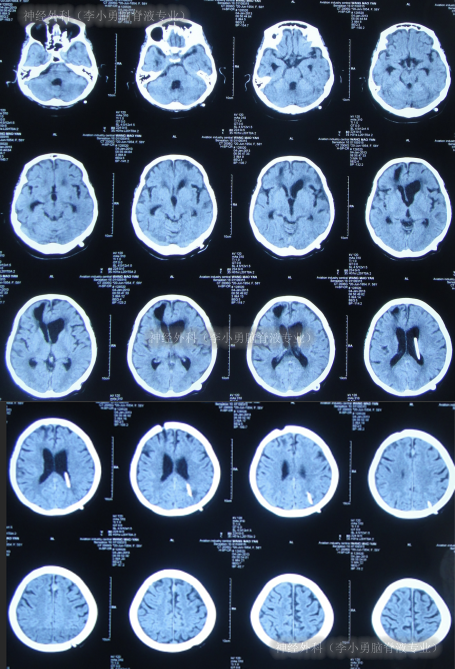

2012年6月14日,入院时:昏迷、体温很高、鼻饲、睡眠差,保留导尿(图-11)。入院后完善血、尿常规、生化全项、胸片、心电图等检查后病情危重,下病危通知。查头颅CT示脑积水(图-12)。

图-12:2012年6月14日头颅CT

住院21天即2012年7月4日,意识已变清楚,查头颅CT示脑室缩小(图-14)。

图-14:2012年7月4日头颅CT

住院27天即2012年7月10日,头颅CT示有少量硬膜下积液(图-15)。

图-15:2012年7月10日头颅CT

脑脊液各项化验均达标后于2012年12月4日,进行脑室腹腔分流术,术前术后头颅CT(图-19)。

图-19:术前术后头颅CT

脑室腹腔分流术后2天即2012年12月6日,查头颅CT示无异常(图-20),查肺部CT示感染进一步减轻(图-21)。

图-20:2012年12月6日头颅CT